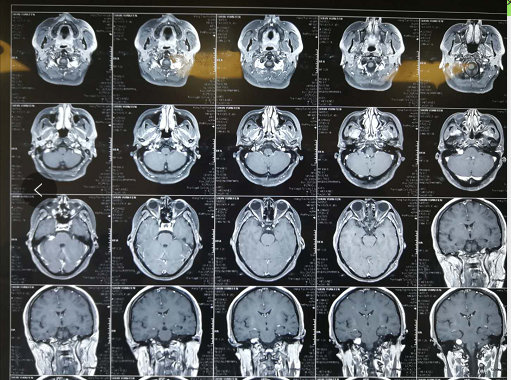

长期耳朵嗡嗡作响,听力下降明显。或许,患上了面瘫几率高达50%的这种病!近日,贵黔国际总医院耳鼻咽喉头颈外科张学渊教授团队,成功为一 …